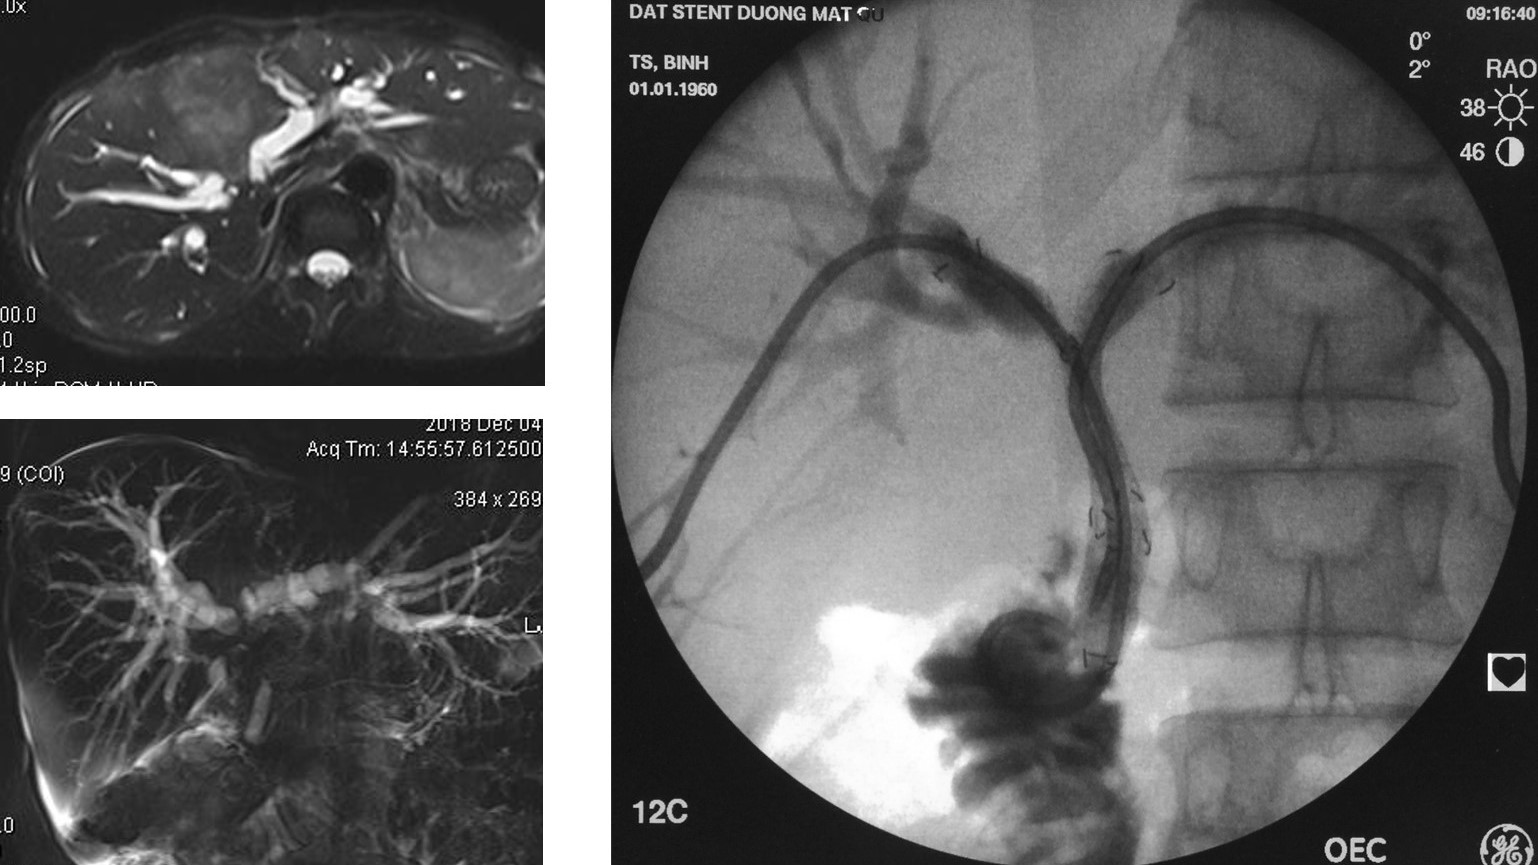

Dẫn lưu và đặt Stent đường mật qua da xuyên gan (PTBD) trong xử trí vàng da tắc mật tại Bệnh viện Trường Đại học Y Dược Huế

Vàng da tắc mật là một bệnh cảnh lâm sàng nặng và thường gặp. Shock nhiễm trùng đường mật là một trong những biến chứng nguy hiểm của tắc mật với tỷ...